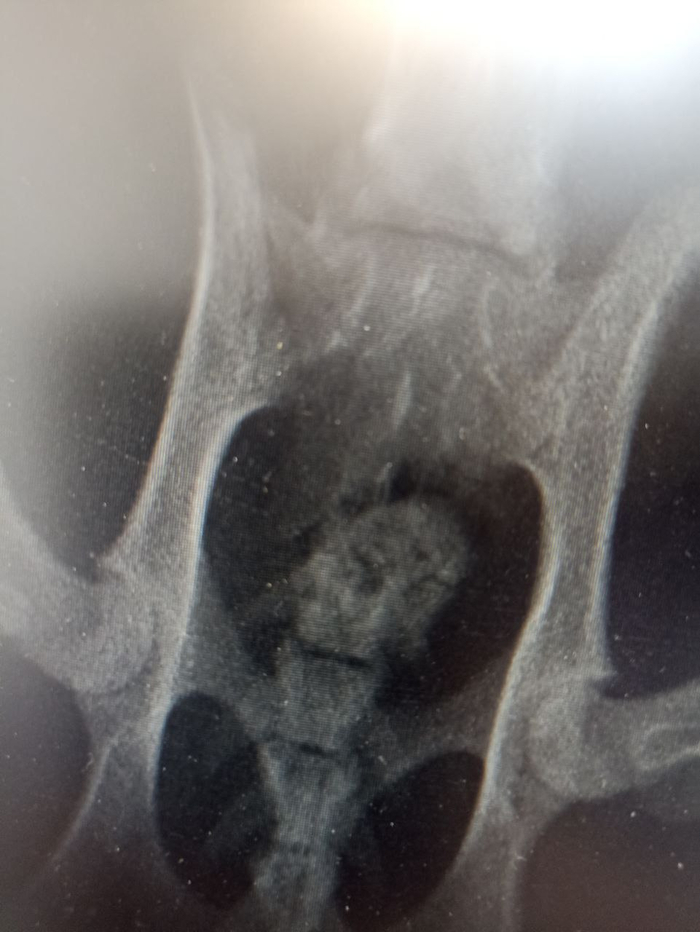

Назначили операцию на 4 мая, врач нашёл входное пулевое отверстие, ему примерно неделя. Пуля давит на позвонки и является источником инфекции. Моча наконец стала светлой, что хорошо.

Мефодий очень ласковый, будет ходить. Тем, кто в прошлом посте рекомендовал усыпить кота, вскоре сможет самостоятельно обоссать ебало. Но пока что кота "выжимает" врач. Кстати, клиника сделала скидку, так как кот уличный, и операция обойдётся в 40т вместо 60т. Кота заодно кастрируют, чтобы два раза не ходить. Ниже чеки, расходы, анализы

В ветклинику подбросили кота в ужасном состоянии, был сильный удар. Писает кровью, ветеринары борются за животное как могут. В теле найдены пули.